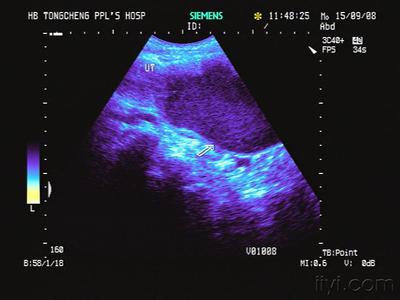

1、通常依据上述症状和体征即可诊断,无需辅助检查。

2、经处女膜膨隆处穿刺,可抽出黏稠不凝的深褐色或陈旧性的血液。